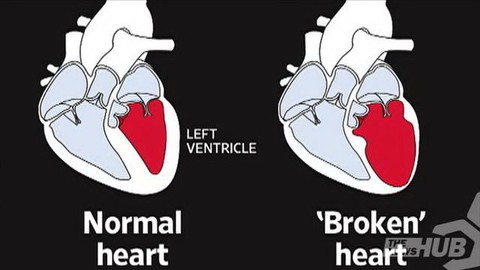

Trong khi nhồi máu là do động mạch vành bị thuyên tắc, thì hội chứng Takotsubo là do tâm thất trái của tim bị biến dạng nên tim không còn bảo đảm được chức năng bơm đủ lượng máu đi nuôi cơ thể nữa.

Ảnh minh họa của tim thường (bên trái) và tim "tan vỡ"